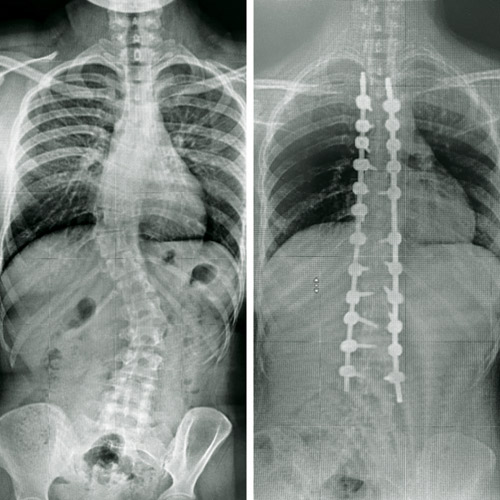

أنهى فريق طبي بمستشفى د. سليمان الحبيب بالقصيم معاناة شابة تبلغ من العمر 18 سنة، كانت تعاني من انحراف خلقي مُضاعف في العمود الفقري «الجنف»، الأمر الذي تسبب في تأجيل المريضة لدراستها. هذا ما أوضحه الدكتور هاني الجهني استشاري جراحة المخ والأعصاب والعمود الفقري الحاصل على البورد الفرنسي ورئيس الفريق الطبي المعالج، والذي أضاف بأن المريضة وصلت للمستشفى برفقة ذويها تشكو من انحناء حاد بالعمود الفقري يصاحبه آلام حادة ومتكررة مع صعوبة التبول، بالإضافة إلى مشاكل دائمة في التنفس. مشيراً إلى أنه تم إخضاغ المريضة لكل التحاليل المخبرية وفحوصات دقيقة بالرنين المغناطيسي (M.R.I) والتصوير المقطعي (C.T Scan)، وقد أبانت الفحوصات أن وضع المريضة يُعد من الحالات المعقدة جداً، نظراً لوجود اعوجاجين الأول ناحية الصدر نسبته 55 درجة، أما الانحراف الثاني فأسفل الظهر بنسبة 40 درجة.

وعن العملية أفاد استشاري جراحة المخ والأعصاب والعمود الفقري بأن الفريق الطبي المعالج قرر التدخل الجراحي بعد مراجعة دقيقة لكل المعطيات الطبية، موضحاً أن العملية استغرقت 6 ساعات متواصلة، وتم فيها تعديل الانحرافين بنجاح تام عبر استخدام أحدث التقنيات وأدوات تثبيت الفقرات والمصنعة من مادة التيتانيوم والكوبلت.